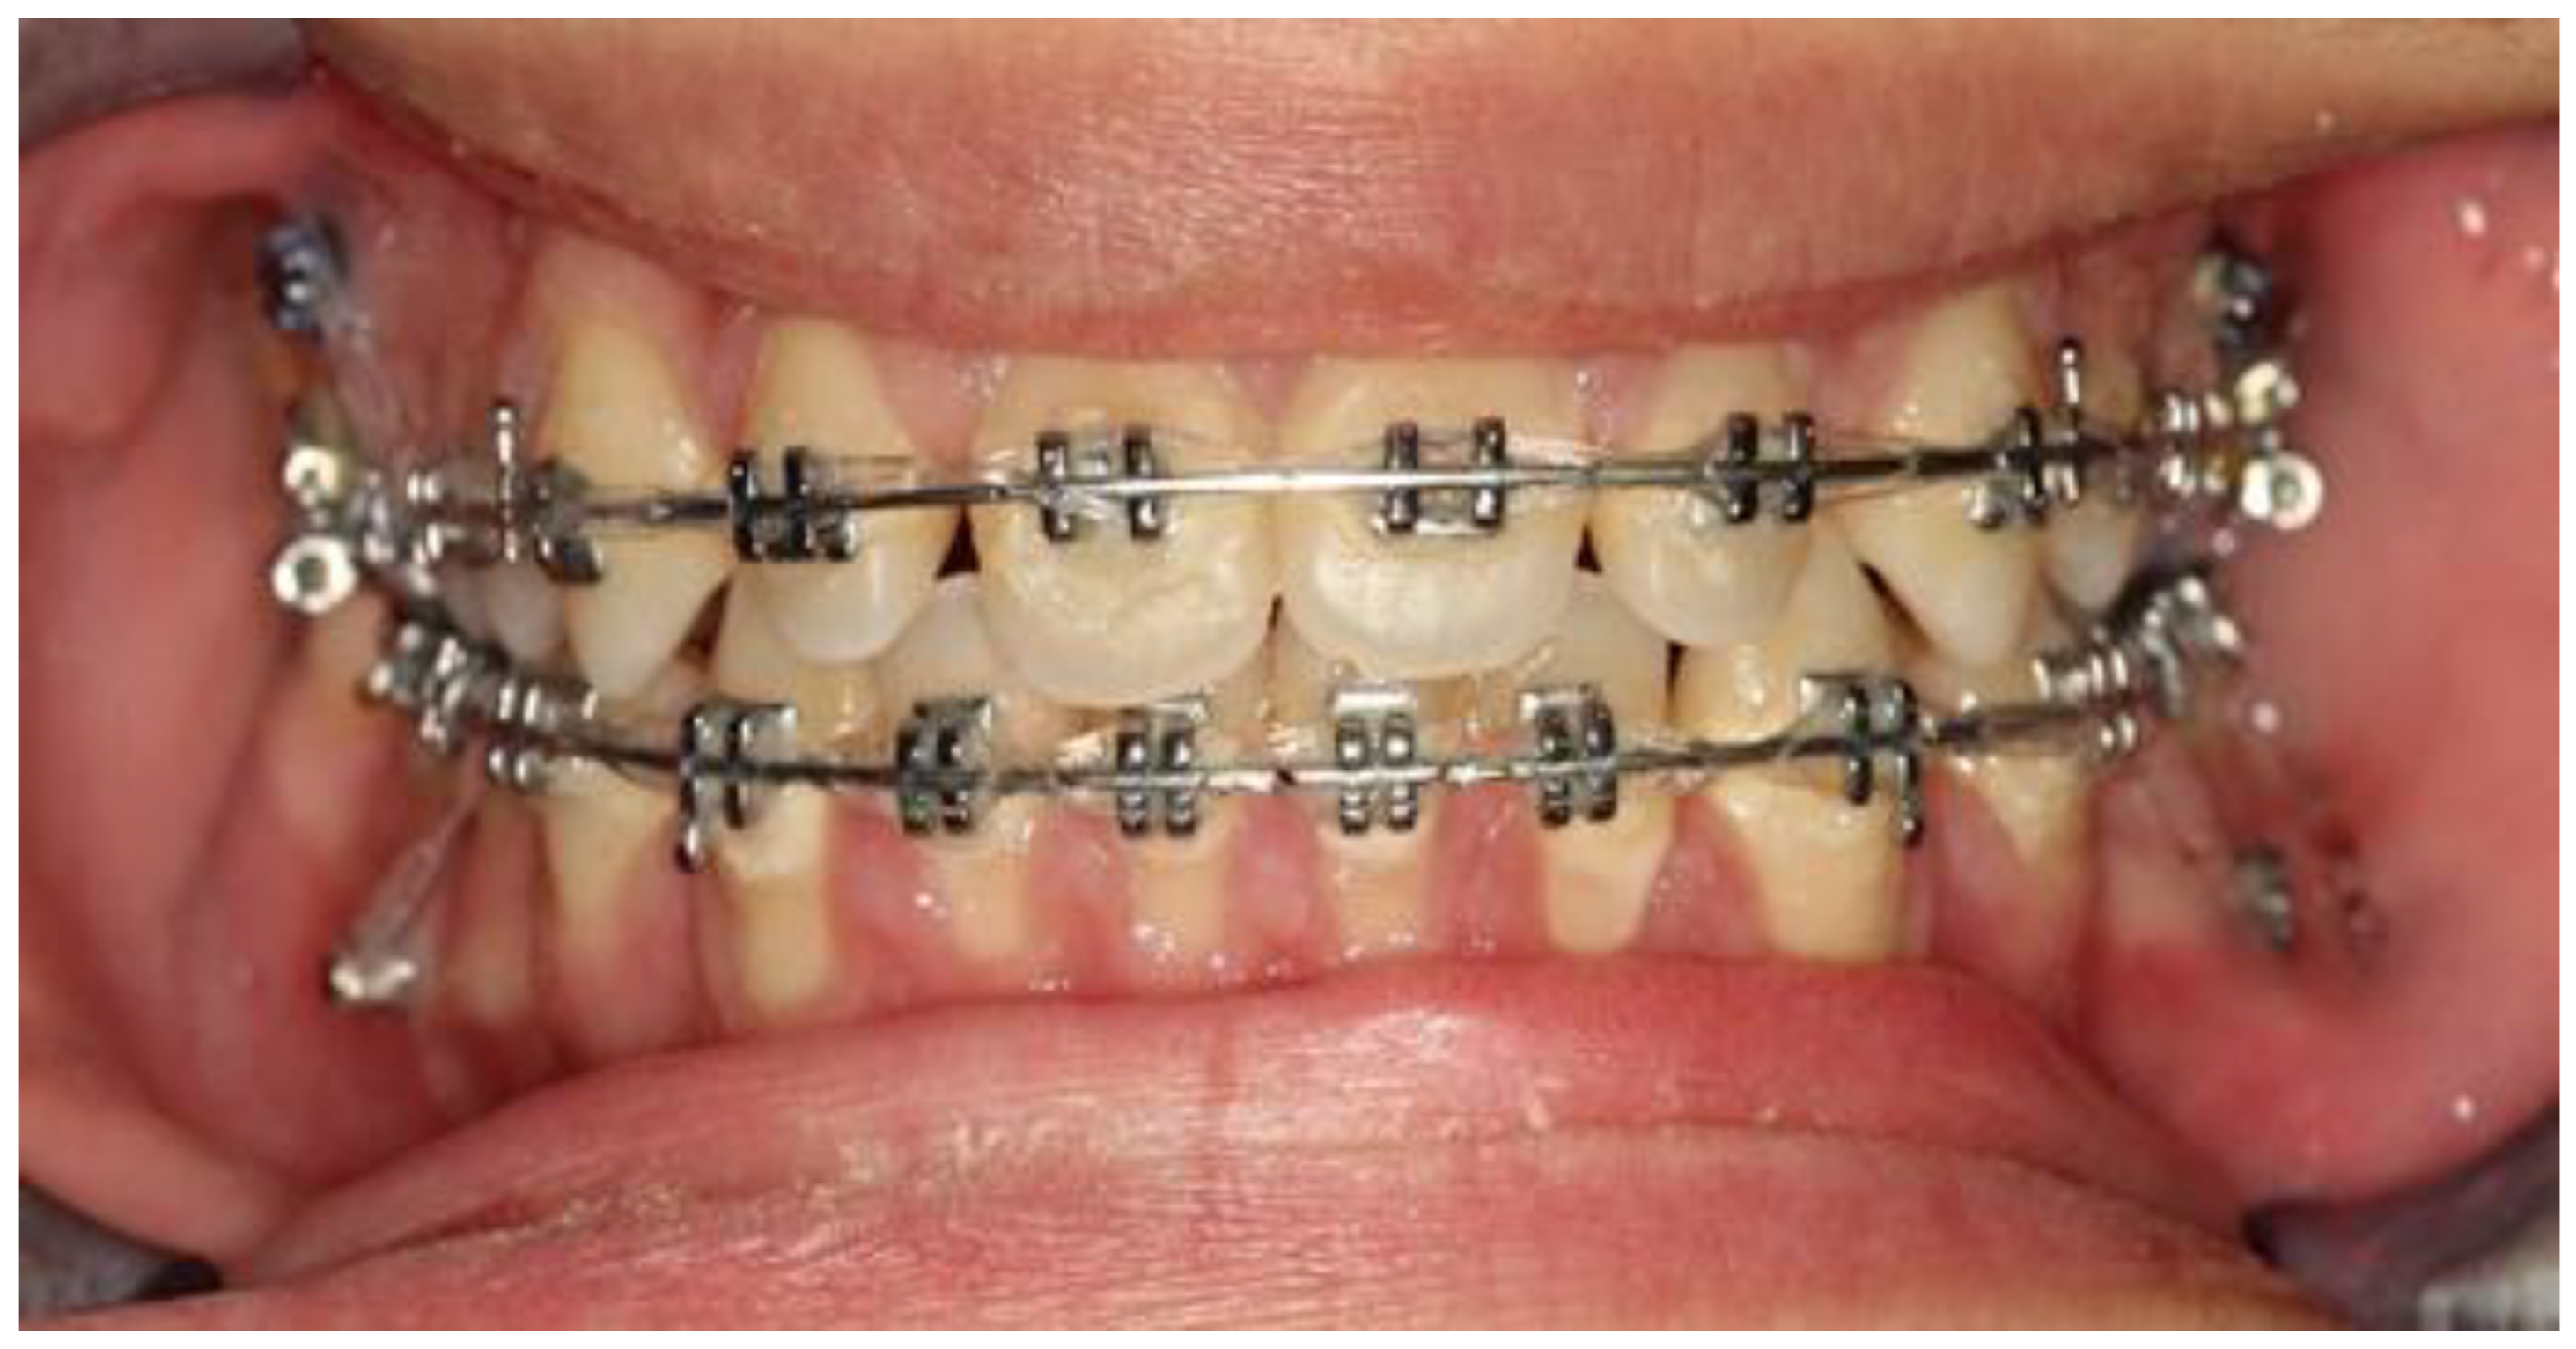

Bimaxillary Dentoalveolar Protrusion Case Treated with Anchorage by Buccally Implemented Mini-Implants Using a 3D-Printed Surgical Guide

3. Results